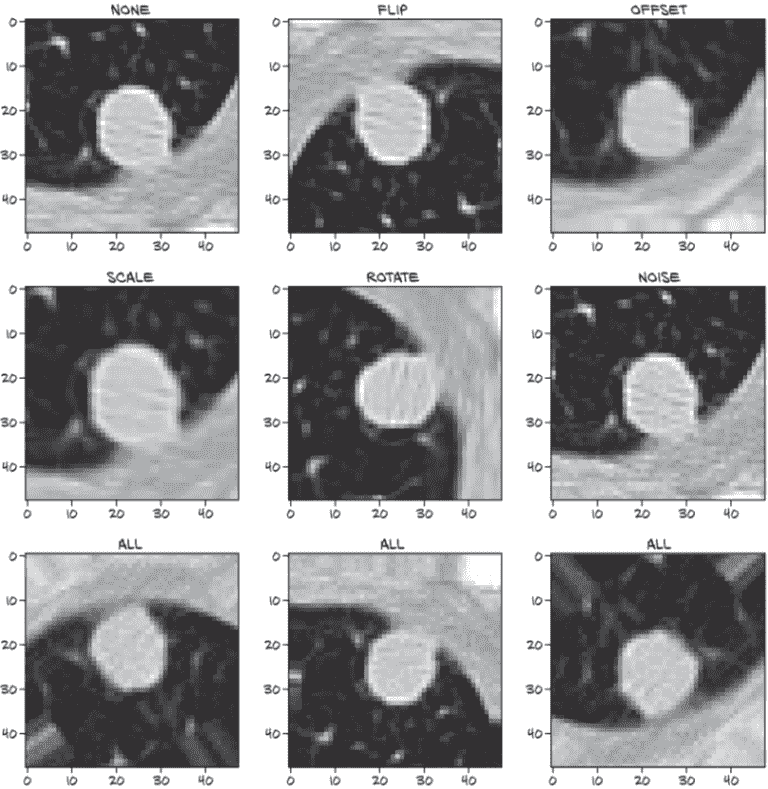

检查增强候选物体

我们可以在图 12.21 中看到我们努力的结果。左上角的图像显示了一个未增强的正候选样本,接下来的五个图像显示了每种增强类型的效果。最后,底部行显示了三次组合结果。

图 12.21 在正结节样本上执行的各种增强类型

由于对增强数据集的每次__getitem__调用都会随机重新应用增强,底部行的每个图像看起来都不同。这也意味着几乎不可能再次生成完全相同的图像!还要记住,有时'flip'增强会导致没有翻转。始终返回翻转图像与一开始不翻转一样限制。现在让我们看看这是否有所不同。